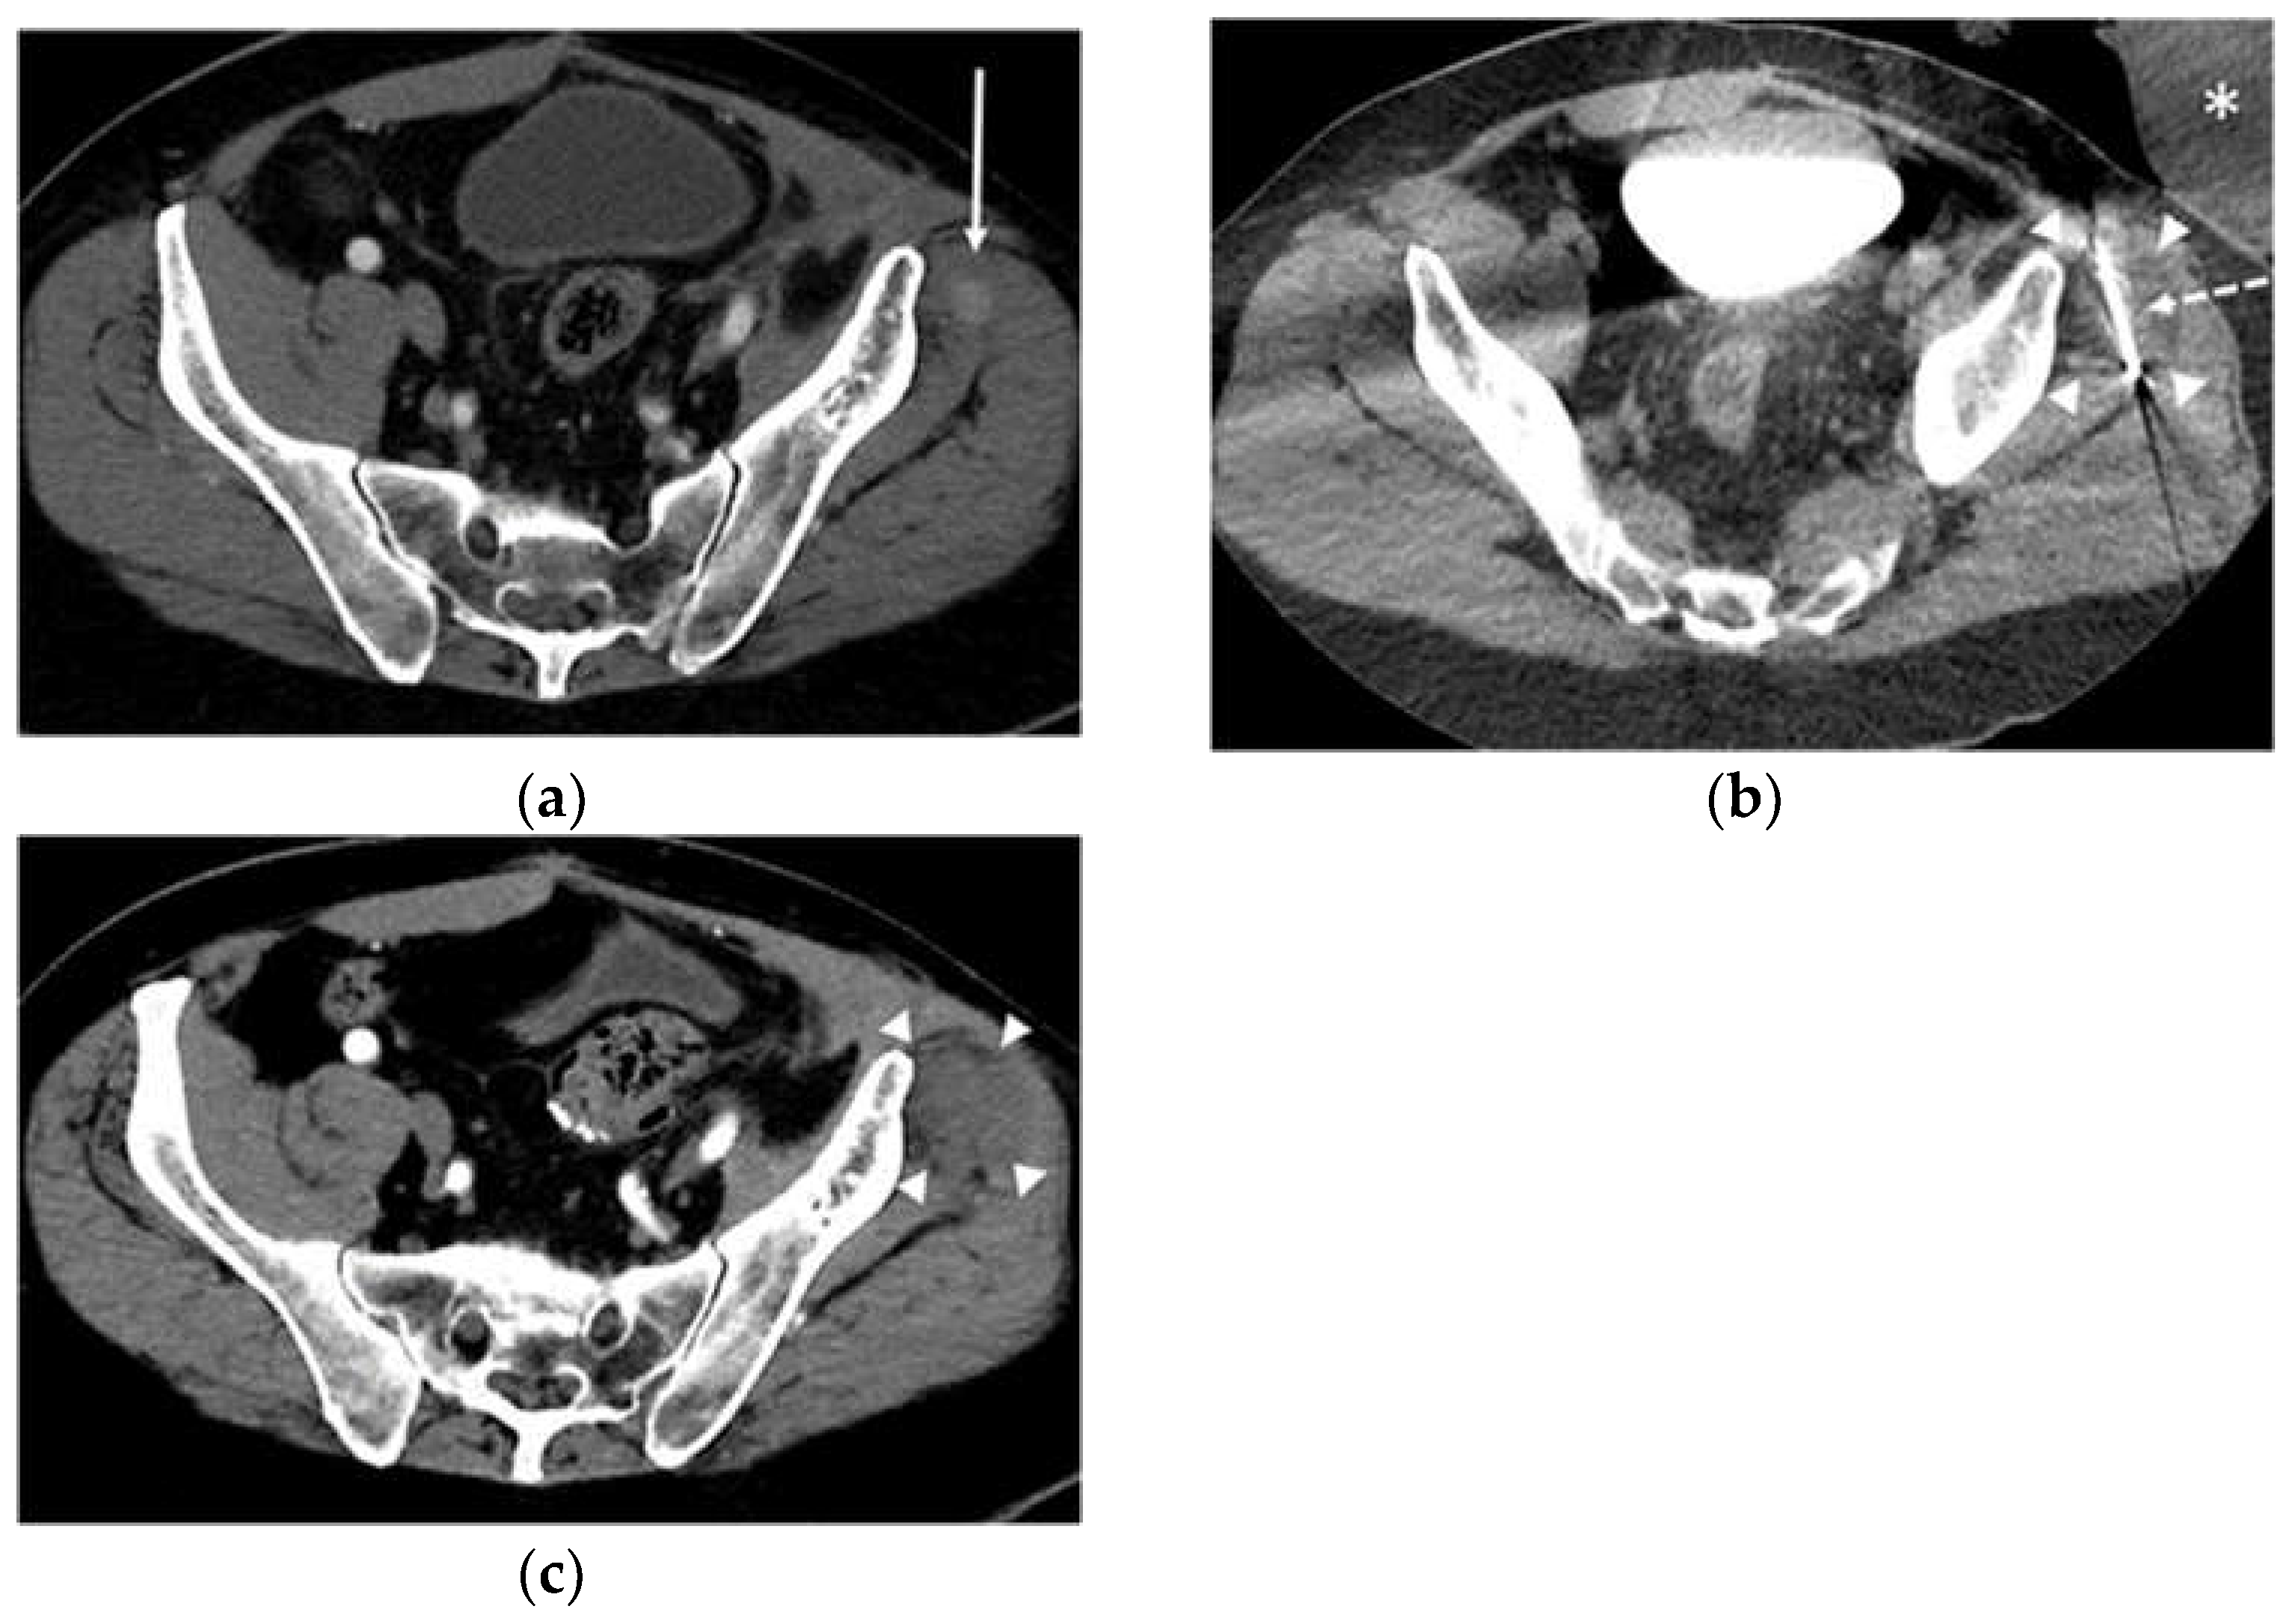

- Dibble, E.H.; D’Amico, K.C.; Bandera, C.A.; Littrup, P.J. Cryoablation of Abdominal Wall Endometriosis: A Minimally Invasive Treatment. Am. J. Roentgenol. 2017, 209, 690–696. [Google Scholar] [CrossRef]